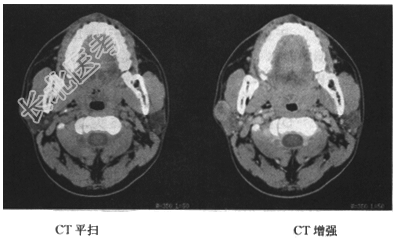

- [材料题] 患者,女。发现面颊部隆起一年余,影像学检查如下图。

- 简答题1、请问该患者最有可能的诊断是什么?

- 简答题2、请问腮腺最常见的良性肿瘤是哪种?

- 简答题3、请问患者是否需要进行细针穿刺活检或其他组织学检查,以帮助确诊?